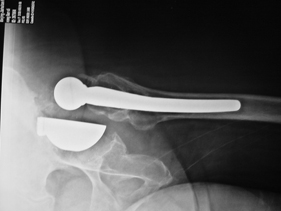

rivision total hip replacement for dislocation and severe bone defect

lateral view of left hip

anterior-posterior view of left hip